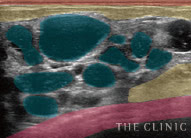

しこりの多発

しこり多発の原因は定かではありませんが、注入回数や体の中で流れることもあるヒアルロン酸の性質との関係性が考えられます。この症例もヒアルロン酸を繰り返し注入した方でした。